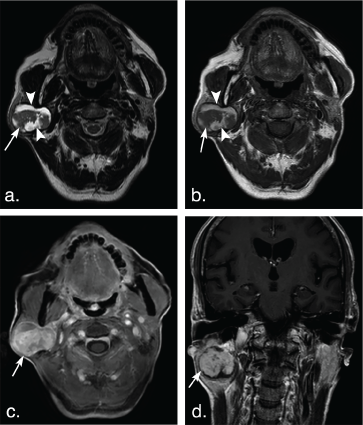

Figure 3: A 14-year-old woman with pleomorphic adenoma in the deep lobe of the right parotid gland. T2 weighted image (a) and T1 weighted image (b) show a well-defined, lobulated tumor (arrows). The tumor shows hyperintense signal on T2 weighted image and hypointense signal on T1 weighted image, marked enhancement (arrow) on axial contrast-enhanced fat-suppressed T1 weighted image (c) but mild enhancement (arrow) on coronal non-fat suppressed T1 weighted image (d). View Figure 3

Figure 4: A 51-year-old man with pleomorphic adenoma in the superficial lobe of the right parotid gland. T2 weighted image (a) and T1 weighted image (b) show a well-defined, heterogeneous tumor (arrows). The tumor shows hyperintense signal on T2 weighted image and hypointense signal on T1 weighted image, marked enhancement (arrow) on axial contrast-enhanced fat-suppressed T1 weighted image (c) but mild enhancement (arrow) on coronal non-fat suppressed T1 weighted image (d). View Figure 4